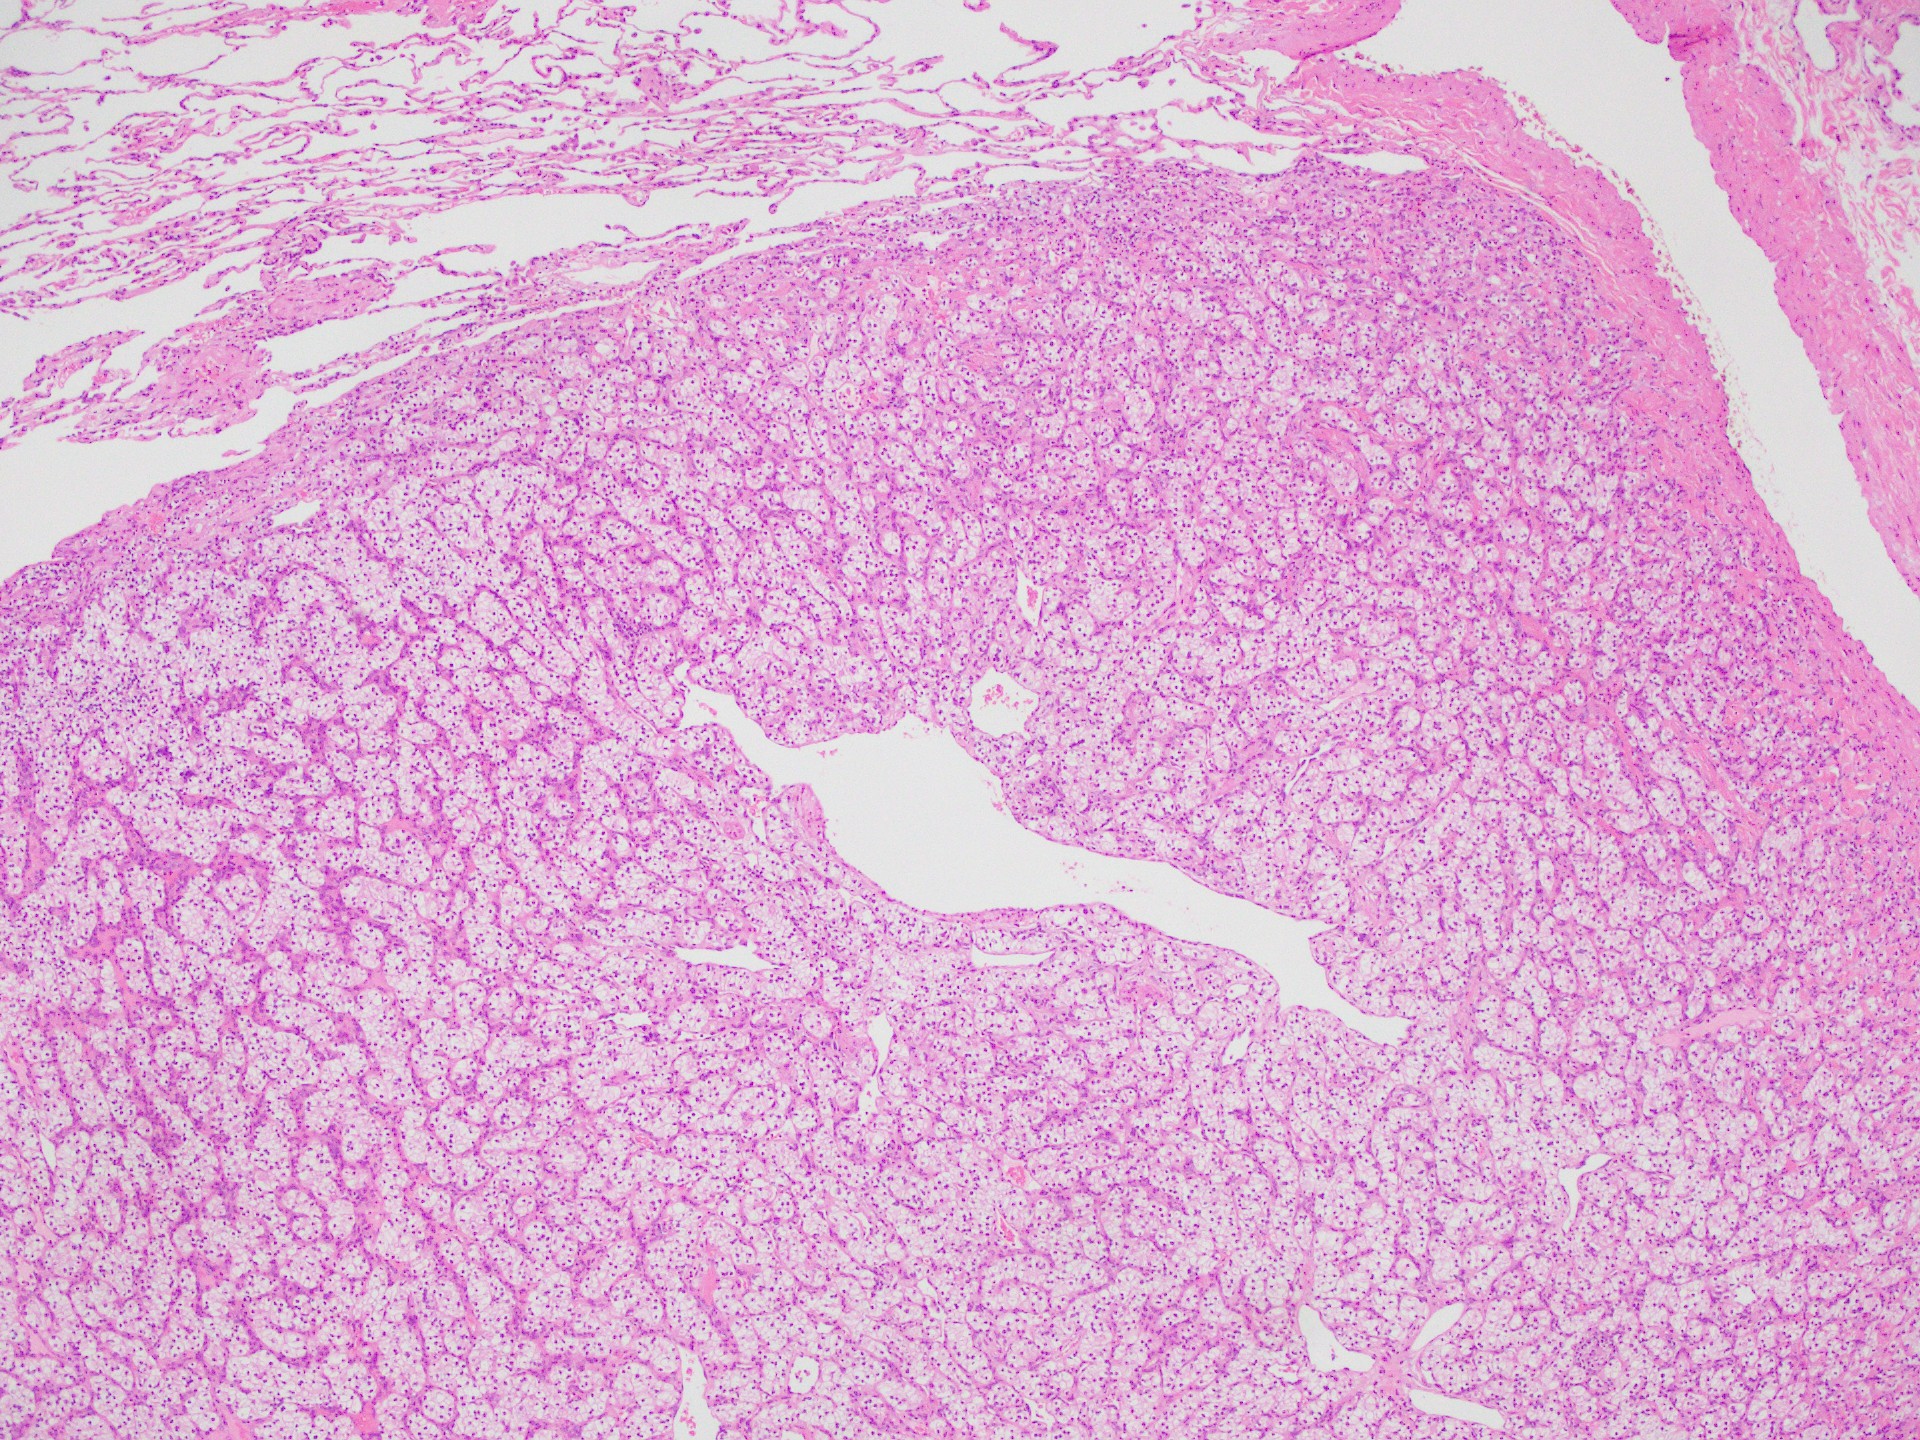

解答:淡明細胞型腎細胞癌の転移

以上の所見および臨床情報より淡明細胞型腎細胞癌の転移と推察できます。

小型類円形核と淡明な胞体を有する細胞が繊細な線維血管網宙に胞巣を形成しています。

肺は全身の静脈血が最初に流れ込むため、血行性転移が起こりやすい臓器です。

そのため、既往歴など臨床情報を把握しておくことも重要と考えます。